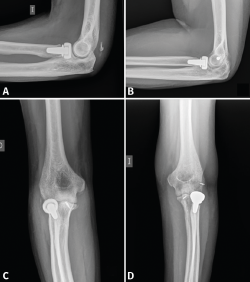

- 2A/2B: son las más frecuentes. La técnica de elección en las fracturas simples en 2 partes es un cerclaje de alambre (obenque) sobre 2 agujas de Kirschner (AK) ancladas a la cortical anterior o colocadas intramedulares. En el primer caso, tenemos riesgo de lesionar las estructuras neurovasculares volares, por lo que no deben sobresalir más de 10 mm; en el segundo caso, el riesgo de que migren proximalmente es mayor(34,35). Se pensó que con este montaje las fuerzas de tensión se transforman en fuerzas de compresión, pero varios estudios realizados no han podido demostrar este principio(36). En las conminutas 2B se recomienda fijación con placa, precisamente para evitar la excesiva comprensión de la cavidad sigmoidea que llevaría a una artrosis precoz. Se recomiendan las placas premoldeadas LCP (locking compression plate). Su efectividad y seguridad están de sobra probadas; sin embargo, al ir en una posición dorsal y ser el cúbito subcutáneo, pueden producir irritación de los tejidos blandos y con cierta frecuencia hay que retirarlas. Aun así, el índice de retirada es mucho mayor en los cerclajes, que puede llegar hasta el 90%(37,38). La alternativa es usar 2 placas laterales de bajo perfil colocadas a ambos lados de la cresta, una medial y otra lateral, que además tienen la ventaja de permitir una fijación bicortical de los fragmentos más proximales. En cualquier caso, los estudios demuestran que ambos métodos tienen buenos resultados y no existen diferencias a corto plazo. Últimamente, se están publicando modificaciones a la técnica clásica del obenque, usando una sutura trenzada de alta resistencia en lugar de alambre(39). En este caso solo tendríamos que retirar las AK y este es un proceso mucho menos invasivo (Figura 8).

- 3A, IB, 2B, 3B: siempre que exista conminución o inestabilidad, el tratamiento de elección será la osteosíntesis con una placa de ángulo fijo LCP, con tornillos de bloqueo adaptados anatómicamente que permiten reducir casi todos los fragmentos.

Figura 8. Ejemplos de fracturas de olécranon en 2 partes (tipo 2A) fijadas con obenque (A y B) y fracturas de tipo 2B fijadas con distintos diseños de placas (C y D).